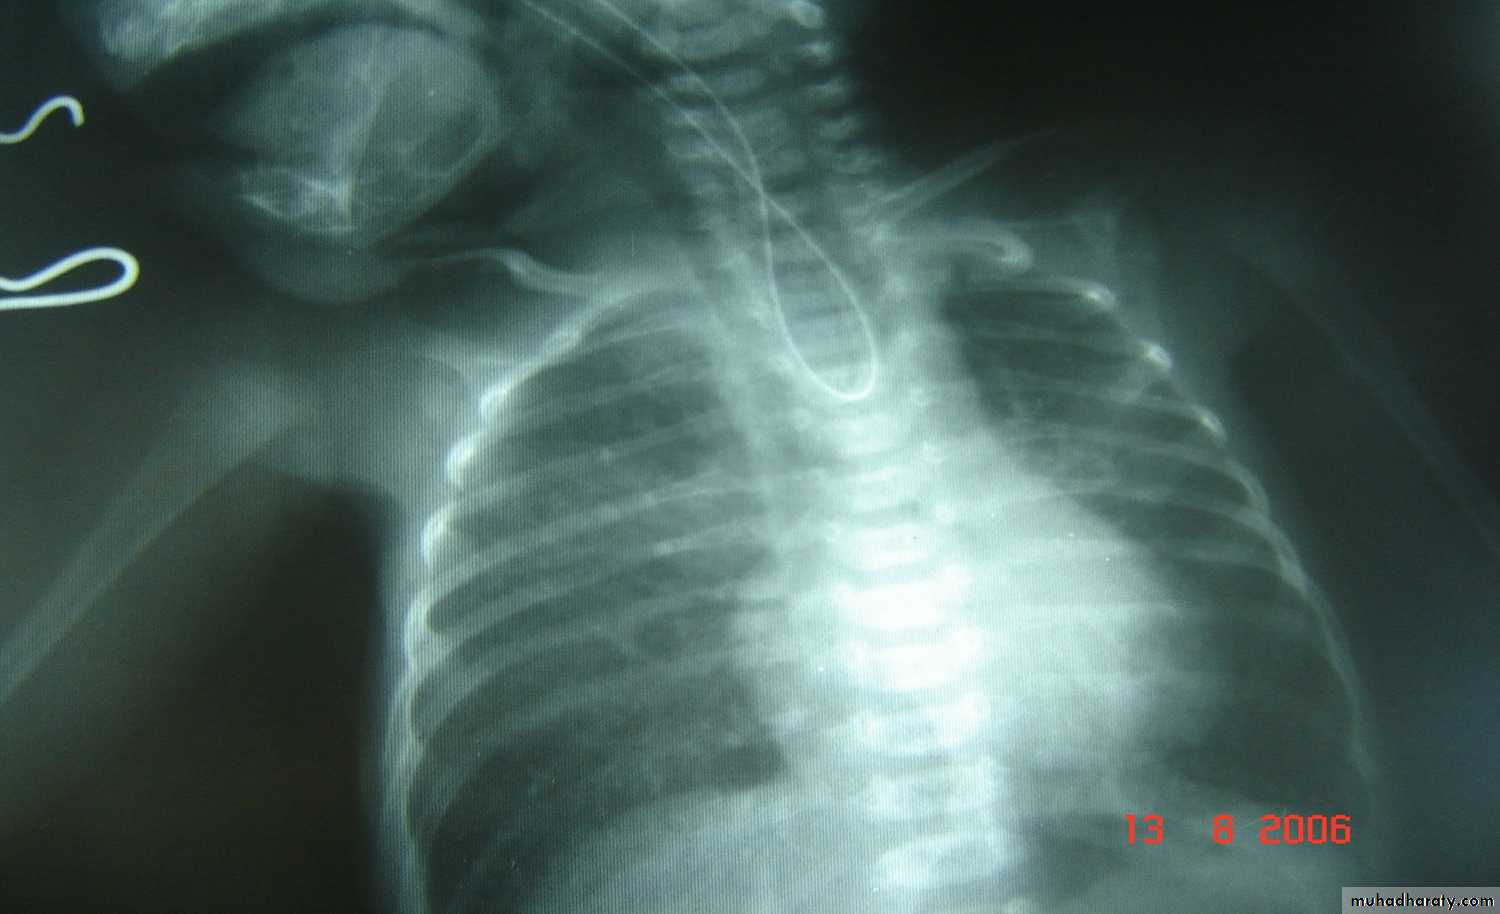

Slide 111-What is the abnormality detected in this x-ray?2- What is the classical presentation of this neonate?